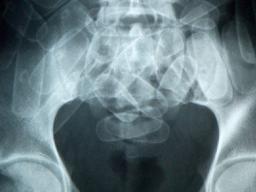

SCHIPHOL - Gisteren werd een dertienjarig Antilliaans meisje door de Marechaussee op Schiphol opgepakt omdat ze cocaïne in haar vagina verstopte en daarmee probeerde het land te betreden. Heel veel treuriger dan dit bericht zal het hopelijk niet worden, maar de geschiedenis leert ons dat bolletjesslikkers hardleers zijn en waarschijnlijk zullen er nog velen vanuit de Antillen en Suriname proberen om via een retourtje Nederland een paar te verdienen.

Ook had ze een langwerpig pakket cocaïne bij zich dat ze vlak voor landing op Schiphol in haar vagina moest verstoppen.